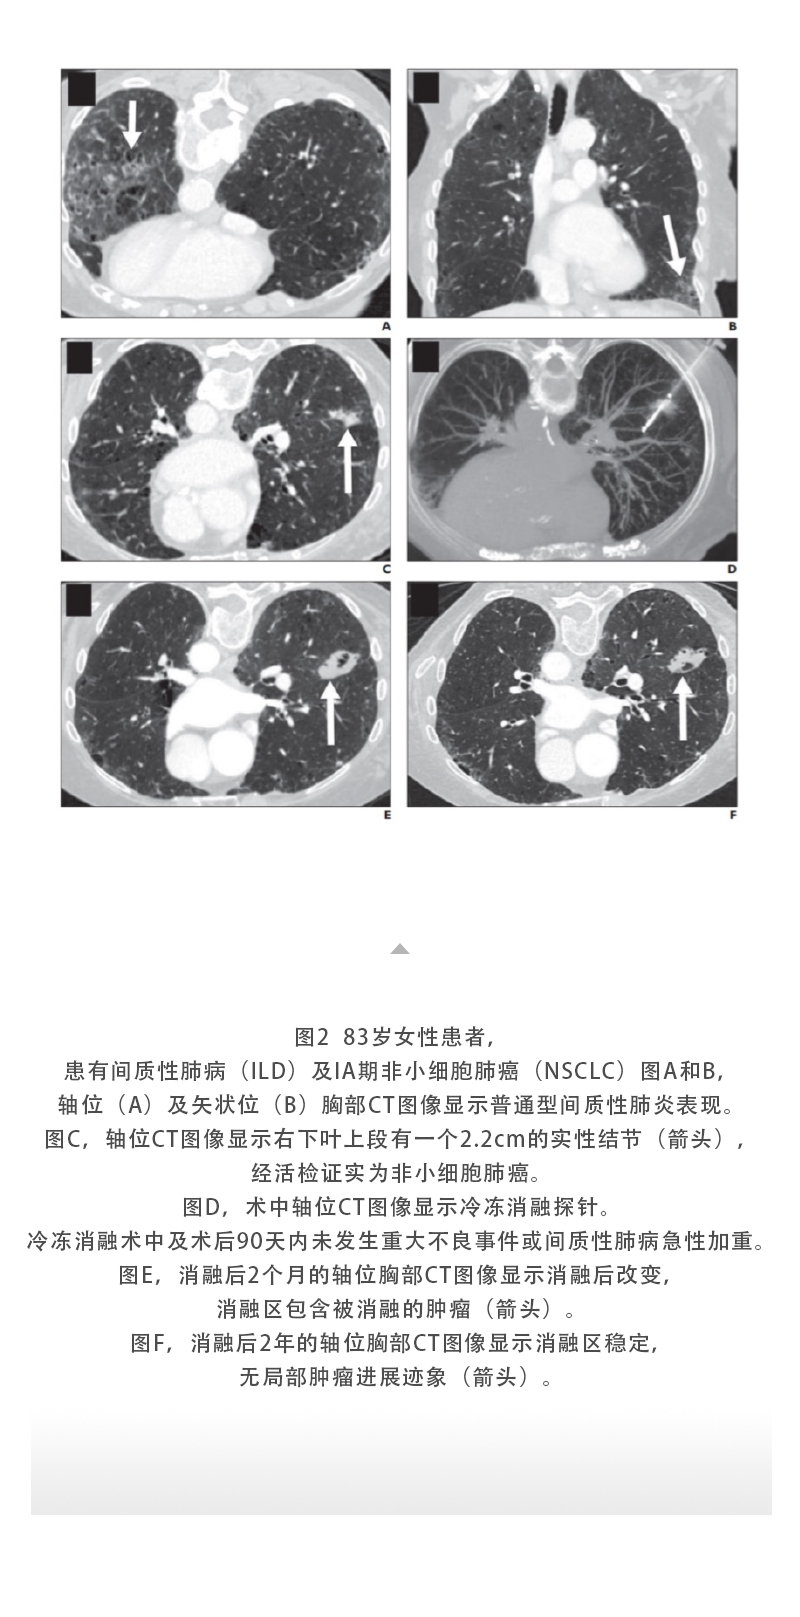

上一頁:【HYGEA·科研資訊】肝癌冷凍消融